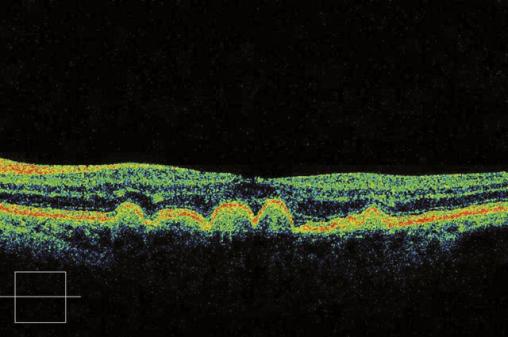

© Jean-François Korobelnik, La Revue du Praticien Tomographie en cohérence optique d'une maculopathie liée à l'âge. L'aspect bosselé correspond aux drusen sous rétiniens.